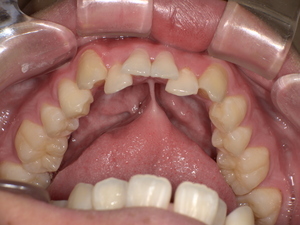

【治療前後の写真】

Before: 舌小帯が短く、舌の可動域が制限されている状態です。このため、舌先を上あごに十分に持ち上げることができません。

[

After: 舌小帯形成術後、舌の動きがスムーズになり、上あごにしっかりと届くようになりました。これにより、発音に必要な舌の動きが改善されます。

]

※写真掲載の際は、患者様の同意を得ています。